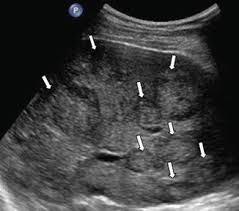

What are these called on a lung ultrasound?

A lines